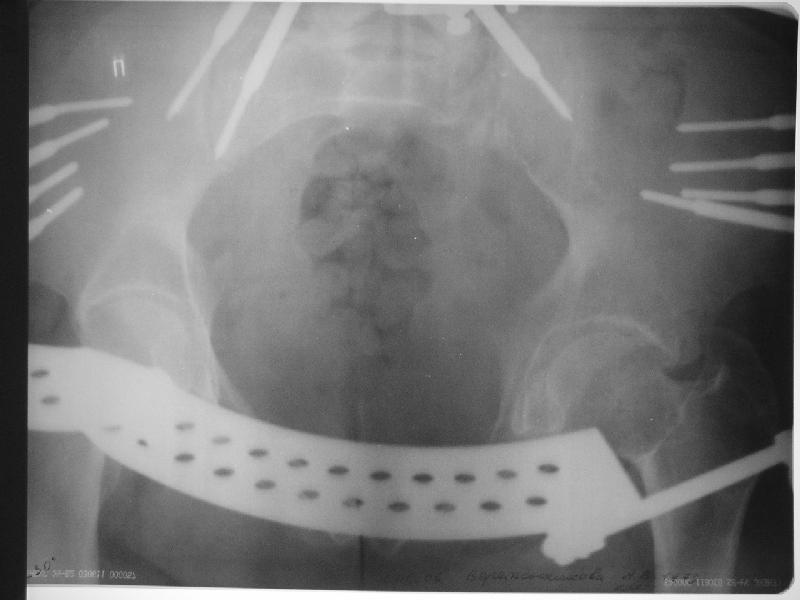

Прооперировали молодую девушку 32 лет спустя 9 мес после травмы. Имелся стойкий болевой синдром, неопороспособность левой н/конечности, моторные и сенсорные нарушения в левой голени и стопе, патологическая подвижность левой половины таза. Первым этапом закрыто в аппарате исправили деформацию ( в течении 2,5 нед). Вторым закрытое введение илиосакральных винтов в крестец (канюллированные 7,2 мм Chm) + туннелизация зоны псевдоартроза спицама Киршнера, реконструкция передних отделов таза, накостный остеосинтез . Аппарат частично демонтирпован, оставлена "передняя рама" После устранения деформации отмечен регресс неврологической симптоматики, уменьшение болевого синдрома. Интересующие вопросы: 1. Прогноз для сращения псевдоартроза крестца. 2. сроки нагрузки весом левой половины таза. Буду очень признателен за ваши мнения по этому поводу.A female 32 y.o. admitted to our unit 9 months after initial injury with pain, inability to bear weight at the left lower limb, sensor and motor disturbances in the left foot and tibia, with mobility of the left hemipelvis.At first closed reduction was performed by an external fixator within 2,5 weeks. After correction her pain decreased and some neurological progress was achieved. Now two iliosacral screws 7,2 mm were inserted, and anterior lesion was fixed by a plate. External fixator was partially unmounted, only anterior frame left in place.Images attached.How would you evaluate chances of healing of the sacrum with the current position?When would you allow weight-bearing of the left leg?THX in advance.